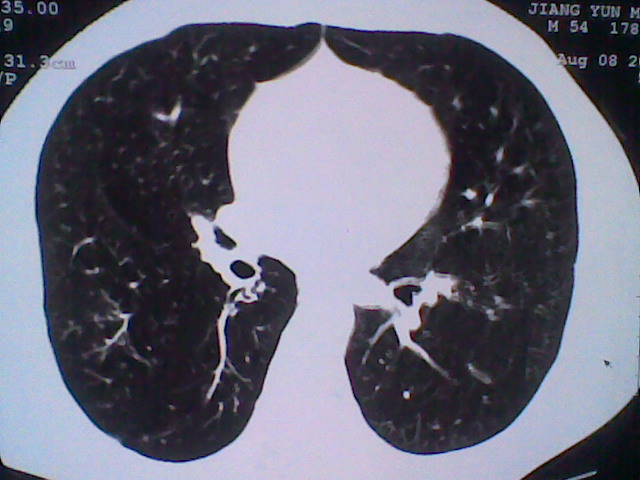

标题: CT21512:支扩伴感染?

患者女。咳嗽数天,咯血半天。

我们报的是支扩伴感染?